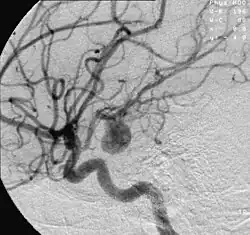

Aneurysm in a cerebral artery,

one cause of hypoxic anoxic injury (HAI).

2. Focal cerebral ischemia – A stroke occurring in a localized area that can either be acute or transient. This may be due to a variety of medical conditions such as an aneurysm that causes a hemorrhagic stroke, or an occlusion occurring in the affected blood vessels due to a thrombus (thrombotic stroke) or embolus (embolic stroke).[21] Focal cerebral ischemia constitutes a large majority of the clinical cases in stroke pathology with the infarct usually occurring in the middle cerebral artery (MCA).[22]